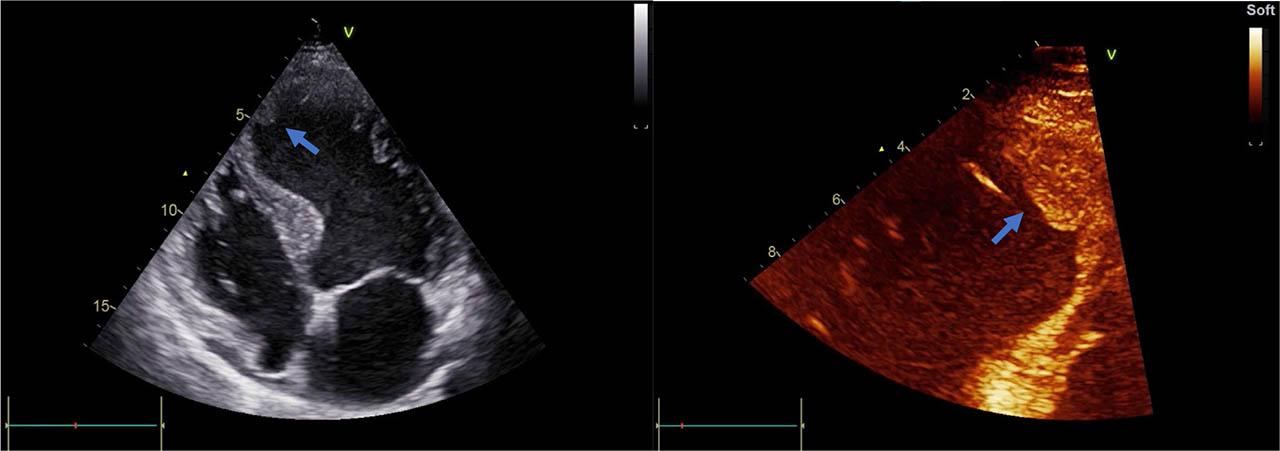

Figure 2